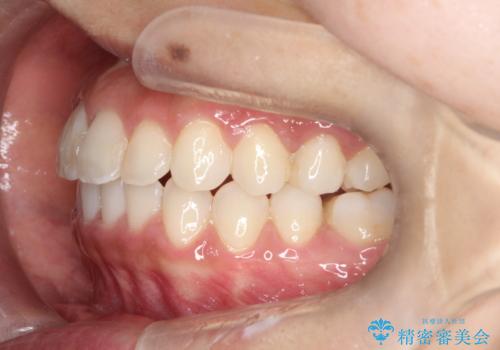

【非抜歯矯正】できる限り前歯を引っ込めたい

- 前歯の凸凹を主訴に来院されました。

非抜歯の範囲でできるだけ前歯を下げることを希望されたため、IPRと臼歯部の遠心移動を行い治療を行いました。当初はインビザラインで治療を行っておりましたが、使用時間を十分に確保できないことで途中からワイヤーを使用しております。

インビザラインは使用時間が不足し治療計画に支障が出る場合、ワイヤーを使用せざる得ない場合があります。(追加の治療費が必要)